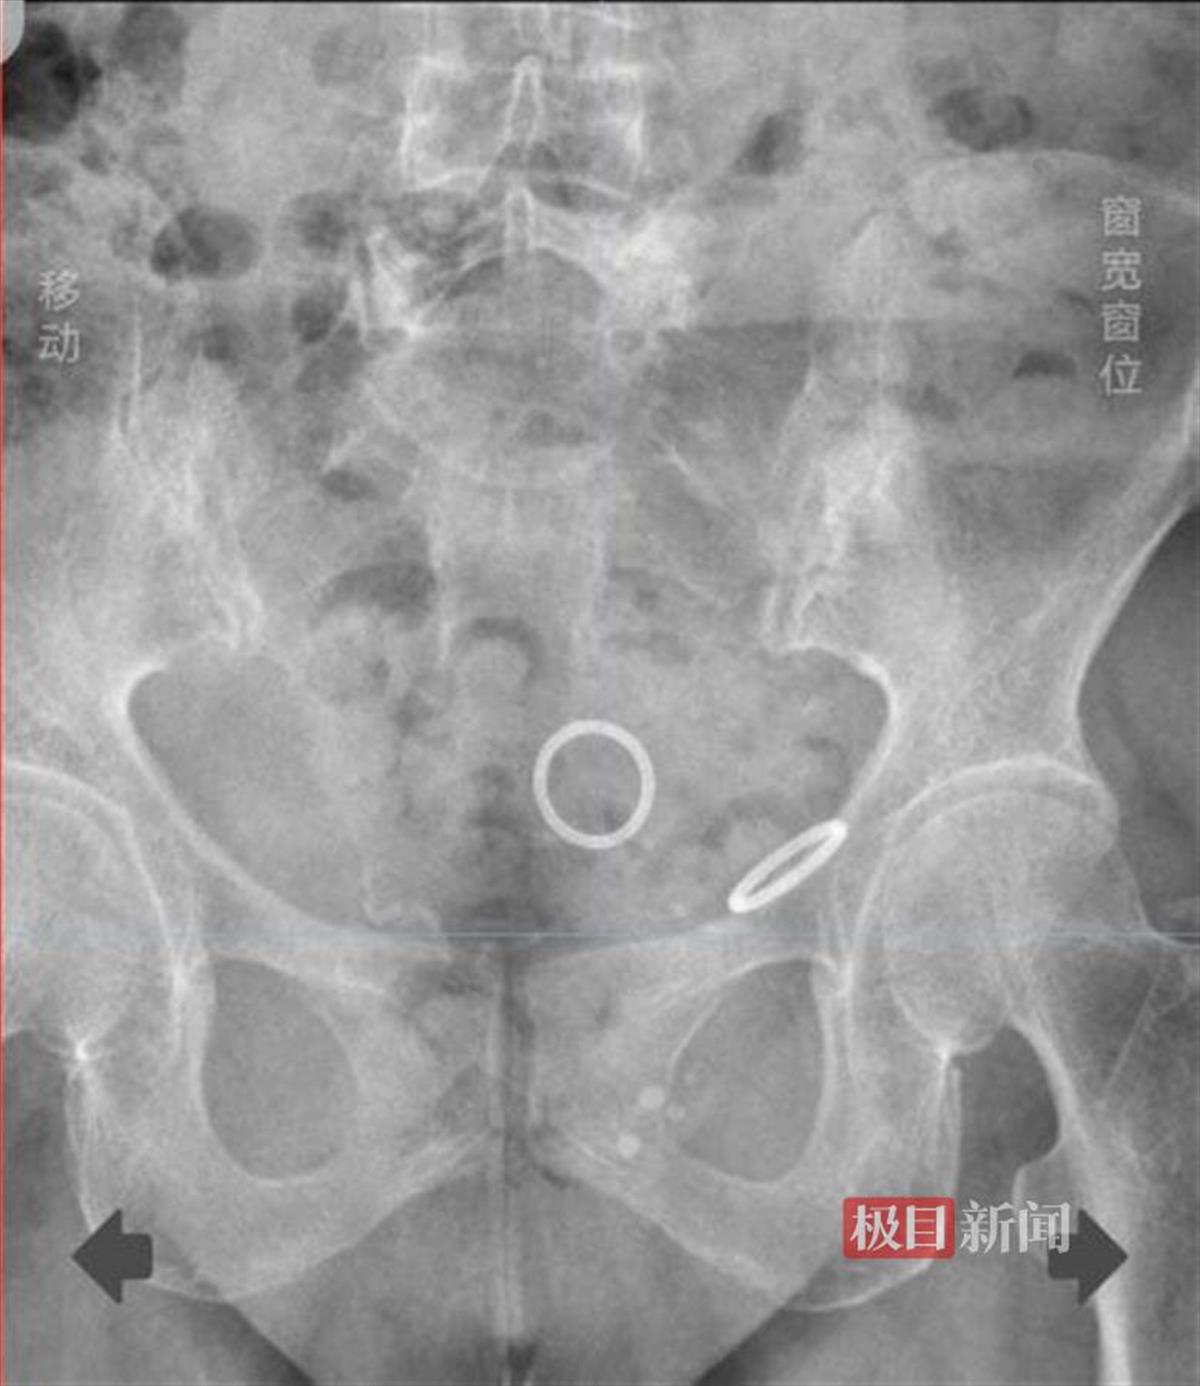

X光下可见患者体内2枚节育环

11月5日上午,在武汉市普仁医院妇科病房内,王女士向查房的医生描述自己的身体状况。三个月前,王女士突然开始出现下腹隐痛,起初并未在意,然而疼痛不仅没有缓解,反倒是愈发严重且持续不断。10月30日,无法再忍受的王女士这才来到家附近的武汉市普仁医院妇科就诊。经过详细检查,妇科副主任医师汪洋发现,王女士体内竟藏着两枚节育环,一枚位于宫腔内,而另一枚竟然已经“迷了路”,游离到了腹腔内,甚至可能已经对腹腔周围的脏器造成了损伤。

11月1日上午,武汉市普仁医院妇产生殖中心主任刘建刚迅速带领团队对王女士的病情进行了分析,并决定实施宫腔镜+单孔腹腔镜联合手术。术中,团队发现宫腔内节育环部分已经嵌入子宫肌层,而腹腔内的节育环则被结肠旁的大网膜紧紧包裹。经过半小时的紧张手术,医生们终于顺利地将两枚节育环取出。术后,王女士的腹痛症状得到了明显缓解。